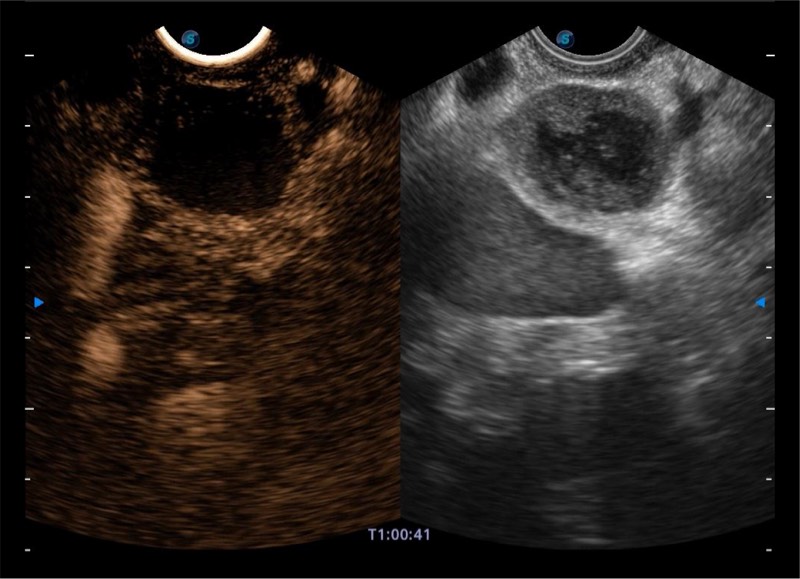

基于二十年的超声技术积累,诸侯快讯官网提供了最新一代的独立超声主机,在提供高质量图像的同时满足多学科使用。具备常见多普勒技术并提供弹性成像、声学造影等高端影像技术。新一代传感器具有更强的抗干扰能力并减少图像伪影。

150°超声扫描角度

4-12MHZ宽频输出